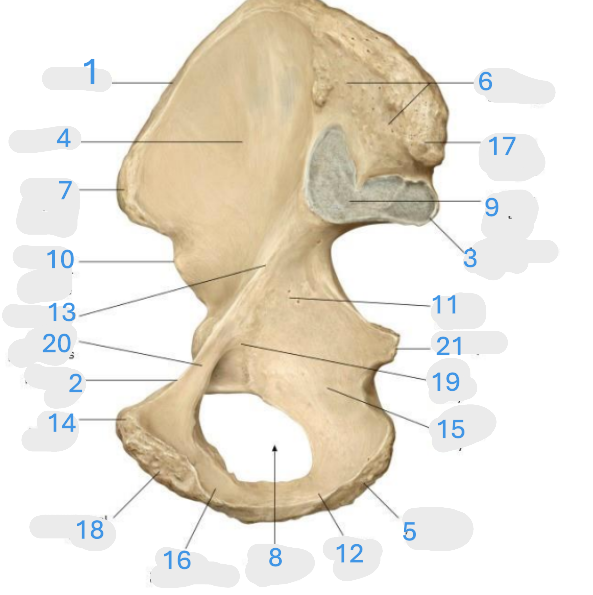

Where is the iliac crest

1

Where is the pubis body

2

Where is the ischium body

3

Where is the obturator foramen

4

Where is iliac wing

5

Where is the ilium body

6

Where is the ischial tuberosity

7

Where is the acetabulum

8

ischial ramus

9

Where is the superior pubic ramus

10

Where is the ischial spine

11

Where is the inferior pubic ramus

12